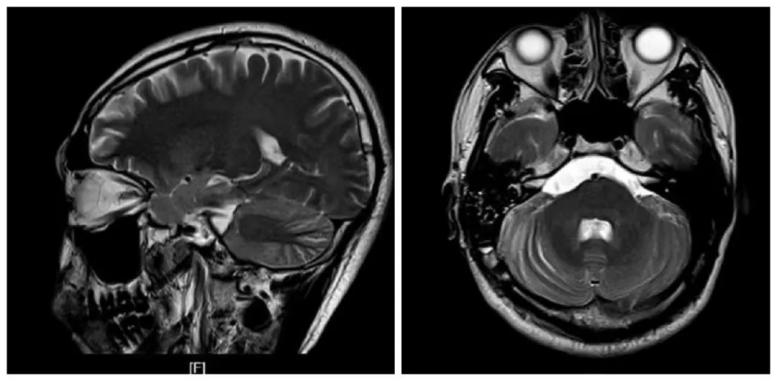

手术通过约4cm的小切口,一次性成功将患者脑干左右两侧及天幕上方的肿瘤完全清除,神经及血管均未损伤,术后患者无高烧症状、无后遗症,已康复出院。

手术后